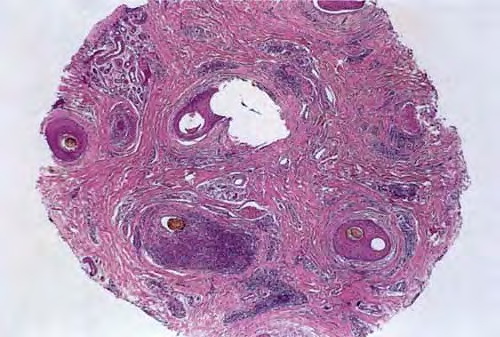

Read MoreForeign body reaction = ارتكاس للجسم الاجنبي Foreign Body Reactions Foreign substances, when injected or implanted accidentally into the skin, can produce a nonallergic foreign-body reaction or, in persons specifically sensitized to them, an allergic response (. In addition, certain substances formed within the body may produce a nonallergic foreign-body reaction when deposited in the […]